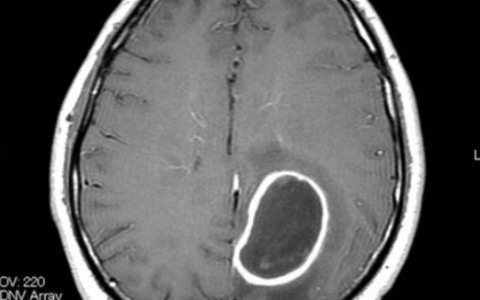

抗NMDA受体脑炎可能与12岁以上女性患者的肿瘤,特别是卵巢畸胎瘤有关。高达67%的患者脑MRI表现正常,脑电图在90%的患者中是异常的,但这些发现为非特异性改变。诊断有赖于脑脊液中NMDA受体抗体的存在来证实。